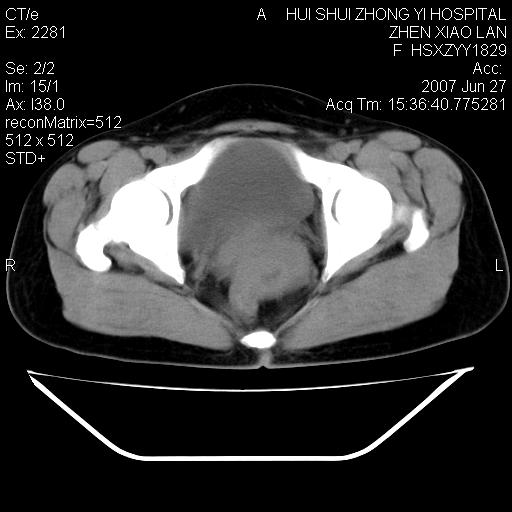

以下是引用还珠格格在2007-6-28 15:15:00的发言:[br]子宫明显增大,偏向盆腔右侧,密度均匀,和子宫同密度, 考虑 子宫肌瘤可能性大 建议增强 除外子宫平滑肌肉瘤。

以下是引用dyqct在2007-6-28 15:41:00的发言:[br]考虑多发子宫肌瘤可能性大,建议进一步增强检查。